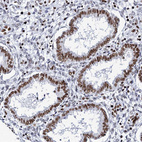

Immunohistochemical staining of human cerebral cortex shows strong nuclear positivity in neurons.